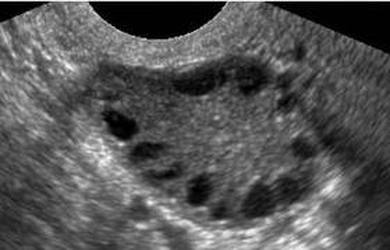

Kiedy ponad pół roku temu lekarz mi zasugerował, że moje koralowe jajniki z PCO są w opłakanym stanie lekko się podłamałam. Tyle lat leczenia, diet, suplementów, ziółek, zdrowego trybu życia, a te patologiczne parzyste narządy staczają się do rynsztoka płodności. Nie wiem czy byłam bardziej wściekła, smutna czy zrezygnowana. necklace-silver-chaplet-model-ornamentMieszkając za granicą i posiadając takie nad produktywne, nadgorliwe i nadpobudliwe w produkcji torbieli jajniki szanse na ciąże są równe wygranej w totolotka. Oglądając obraz USG z moim ginekologiem miałam wrażenie, że niedługo to te jajeczka się tam nie będą mieścić. Zupełna niesubordynacja. No i jak tu zaradzić. Przecież nie da się wysłać ich do ośrodka szkolno-wychowawczego w celu resocjalizacji. Może gdyby była dostępna jakaś psychoterapia, albo chociaż jakaś grupa wsparcia. No nie ma absolutnie żadnych dostępnych metod wychowawczych. Zero posłuchu i autorytetu. Dlatego, doszliśmy z lekarzem do wniosku że nie ma na co czekać – czas na laparoskopię. Trzeba było uderzyć z grubej rury i wytoczyć ciężką artylerię w postaci groźnie brzmiącego zabiegu kauteryzacji.